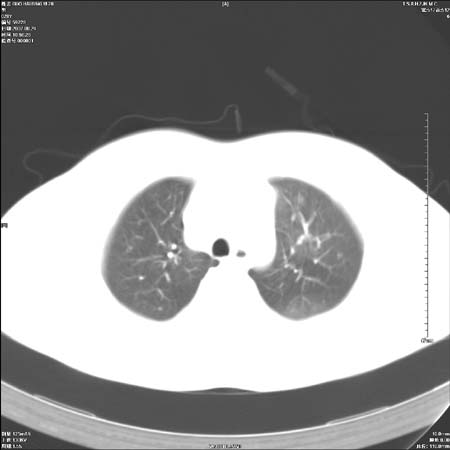

男性,28岁,体检发现左肺病变,患者只有背部隐痛感,哀哉,真不忍心下诊断啊。

左肺门区软组织肿块,左肺上叶支气管开口消失,纵隔内见肿大淋巴结,考虑左中心型肺部,可以做纤支镜取病理确认.

左肺肺门区肿块影,分叶明显:诊断肺癌应该没有疑问。

我觉得定位中央型还是周围型这个有点难。

本例倾向周围型肺癌

鉴别:中央型肺癌-肿块那么明显一般合并节段肺不张或阻塞性炎症。

本例肿块边缘外侧可见左上叶各段支气管。

左肺肺门区肿块影,分叶明显,左肺上叶支气管开口受压,纵隔内见肿大淋巴结,考虑左中心型肺癌。

左侧肺门区见一块状病灶可见分叶,纵隔内及左肺门见肿大淋巴结,应该是周围型肺癌而不是中心型肺癌,原因有以下2点,1未见阻塞肺气肿和阻塞性炎症,这么大肿块如果是中心型肺癌就是未分化型或小细胞型肺癌不出现阻塞性肺不张也应该有阻塞炎症或阻塞性肺气肿,2如果是中心型肺癌临床出现最早的症状是咳嗽(此时可无任何异常影象),而此人这么大肿块只有背部隐痛是体检才发现无法解释.

左肺门区分叶状软组织肿块,纵隔内有肿大淋巴结,诊断肺癌应该问题不大。

直接下肺癌诊断还太早,病灶较大,估计5cm以上,但阻塞性改变及对临近纵隔及支气管侵犯不明显,密度较均匀,弓旁见一单个淋巴结,需要排除炎症性肿块及腺瘤,平滑肌瘤等。